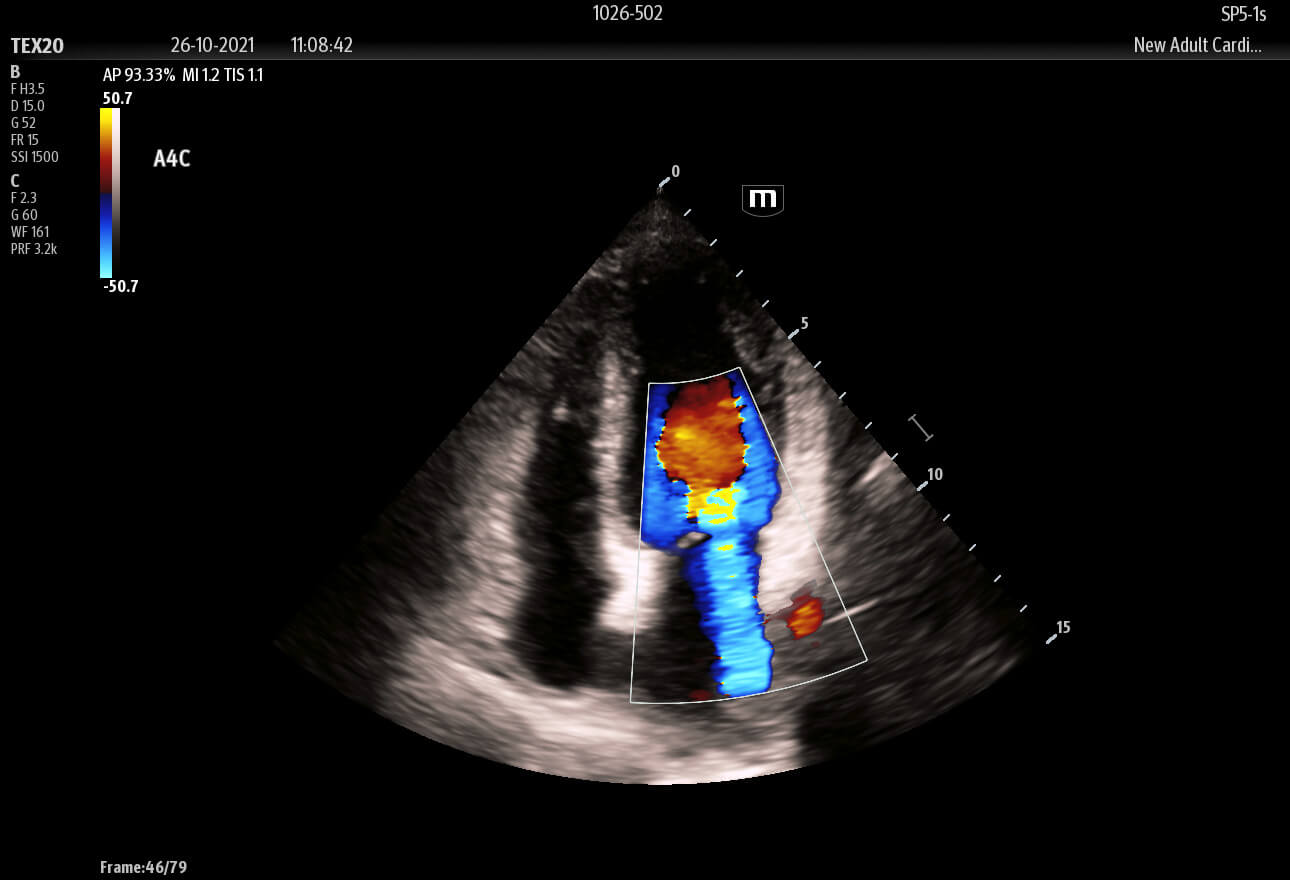

Inspired by the increasing clinical demands of today’s challenging healthcare environment, the touch-based TE X Ultrasound System adopts advanced technologies and integrates them into an innovative, accessible, and patient-centered solution.

The technology-rich TE X Ultrasound System gives clinicians access to market-leading artificial intelligence (AI)-powered Smart Tools, an ergonomically designed system, and proprietary software-based beamformer Zone Sonography Technology+ (ZST+). By incorporating these elements, the TE X Ultrasound System provides access to advanced diagnostic data, the ability to adapt to the various clinical scenarios at point of care, and best-in-class imaging to help them provide a higher standard of care.